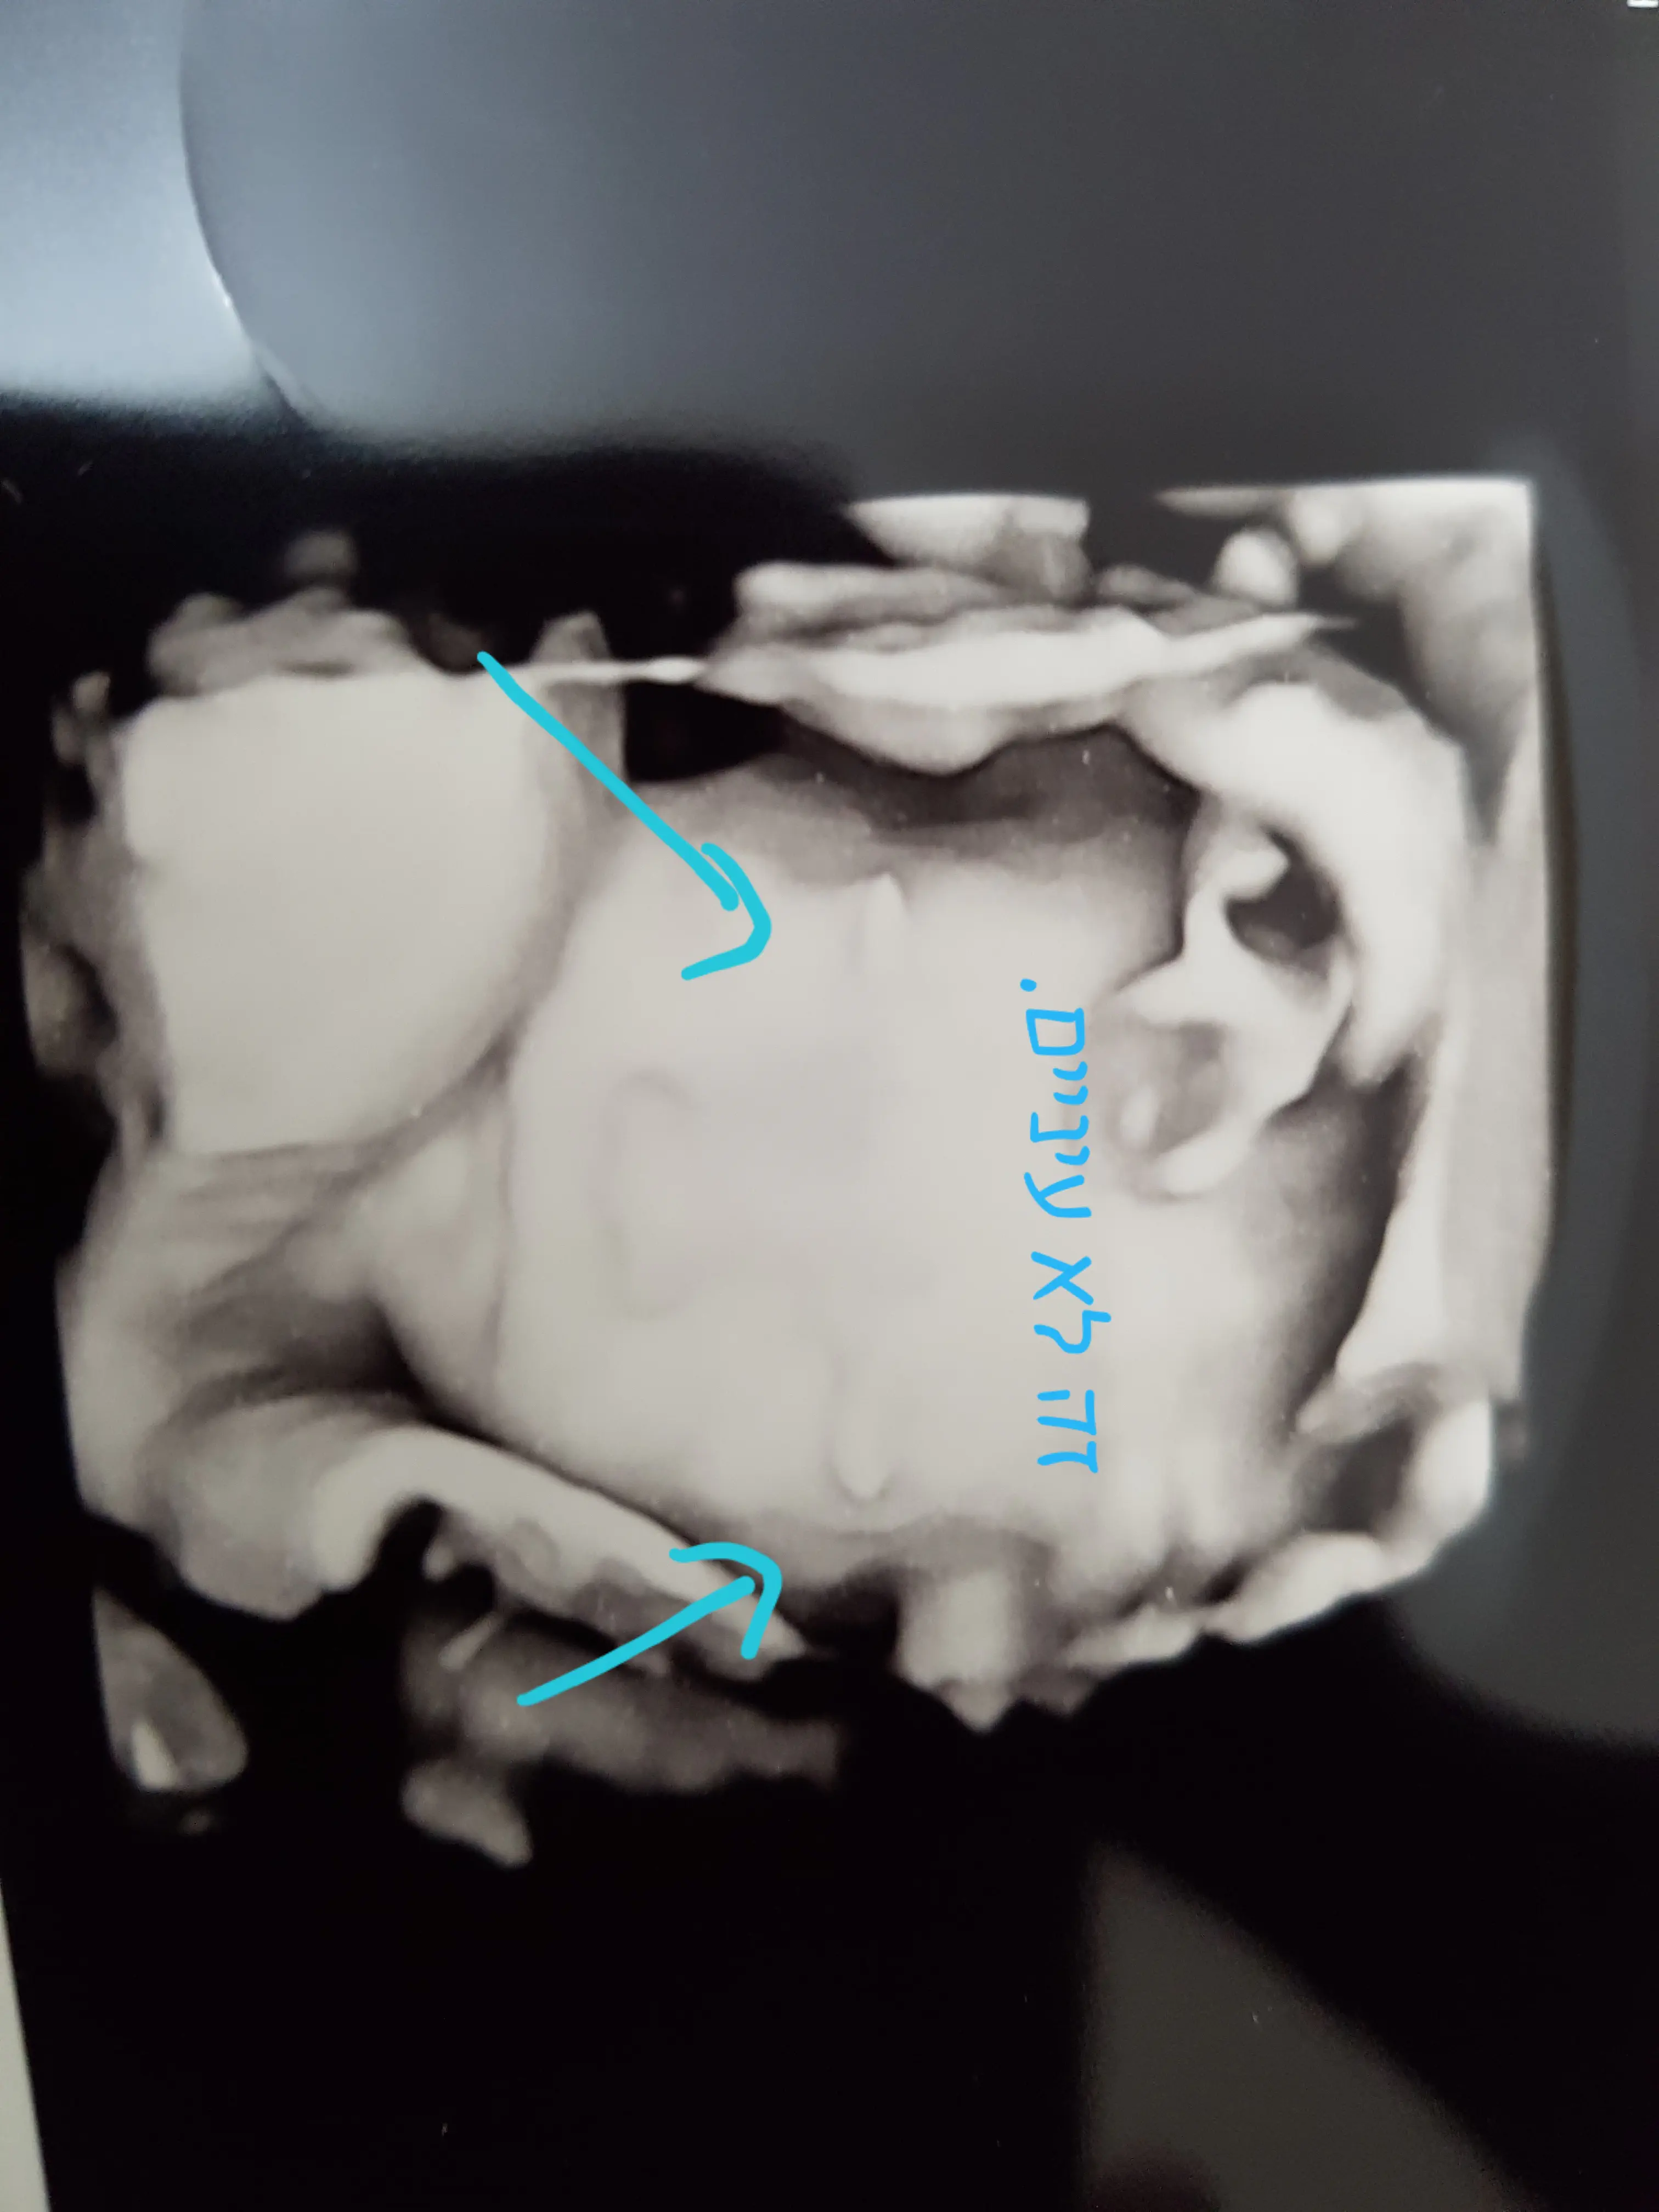

מצרפת תמונה..נסיונות בהריון

אין לי בעיה שתראי את התמונה, שאגיע לאדם שמכיר מקרה כזה.נסיונות בהריון

מצרפת תמונה, אין לי בעיה שהתמונה תתפרסם.נסיונות בהריון

ברוך ה' הריון שני, עברתי אתמול סקירה שניה.

הרופא אמר שהכל ניראה תקין, מלבד הגבות. הוא אומר שמעולם לא נתקל בזה.

בגבות בולטות כלכך באולטרסאונד, בכלל לא ראה דבר כזה

עברתי סקירה שניה, בה הרופא לא ראה ממצא חריג ברוך ה" מלבד הגבות.

הוא אומר שהגבות מאד בולטות. אף פעם לא ראה גבות כאלה. בטח לא בסקירה..